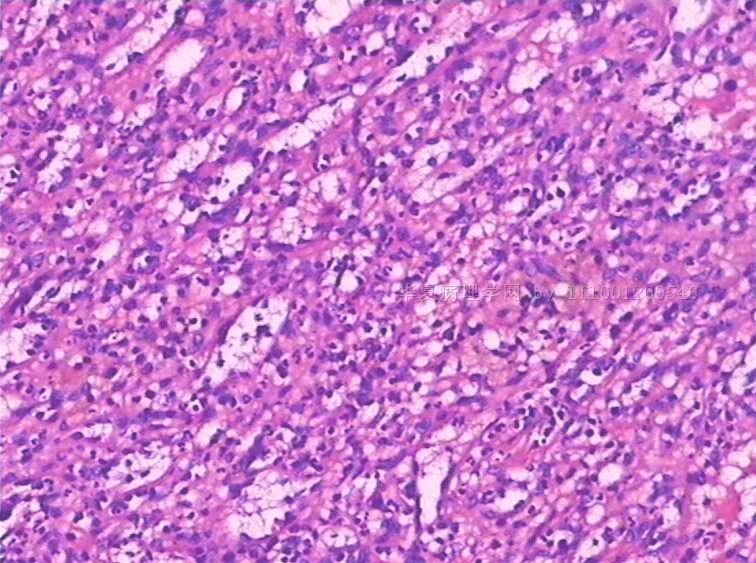

性别:

女

年龄:

49

标本名称:

反复发热,全血细胞下降1月余.CT示肝、脾肿大。骨髓检查:增生活跃,红系增高。

手术所见:脾巨大,内有梗死。肝表面光滑、肿胀。肝门淋巴结肿大,无腹水。

巨检:脾切除一个,20×15×8cm.切面灰红,有多个灰白区,最大8×6×3cm,呈楔性,小者绿豆大小

见到一些异型细胞,细胞质几乎看不到。考虑为淋巴造血系统肿瘤,脾脏原发淋巴瘤可能。

是好多组织细胞吗?期待中